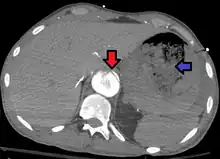

Aorto enteric fistula and aortic dissection of the thoracic aorta. Arrow shows the flap in the aorta. Heterogeneity is blood in the stomach |